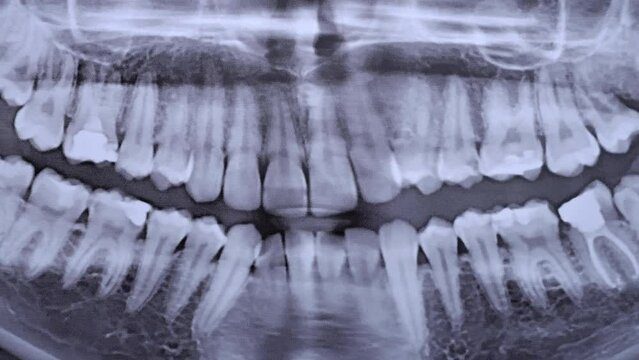

Radiographic Analysis

Advanced imaging provides objective insight into bone density. Cone beam computed tomography (CBCT) scans offer three-dimensional views of the jaw, revealing volume, thickness, and density distribution. Panoramic X-rays provide broader context but lack the detail needed for precise planning. Radiographic analysis guides implant size, placement angle, and the need for augmentation procedures.